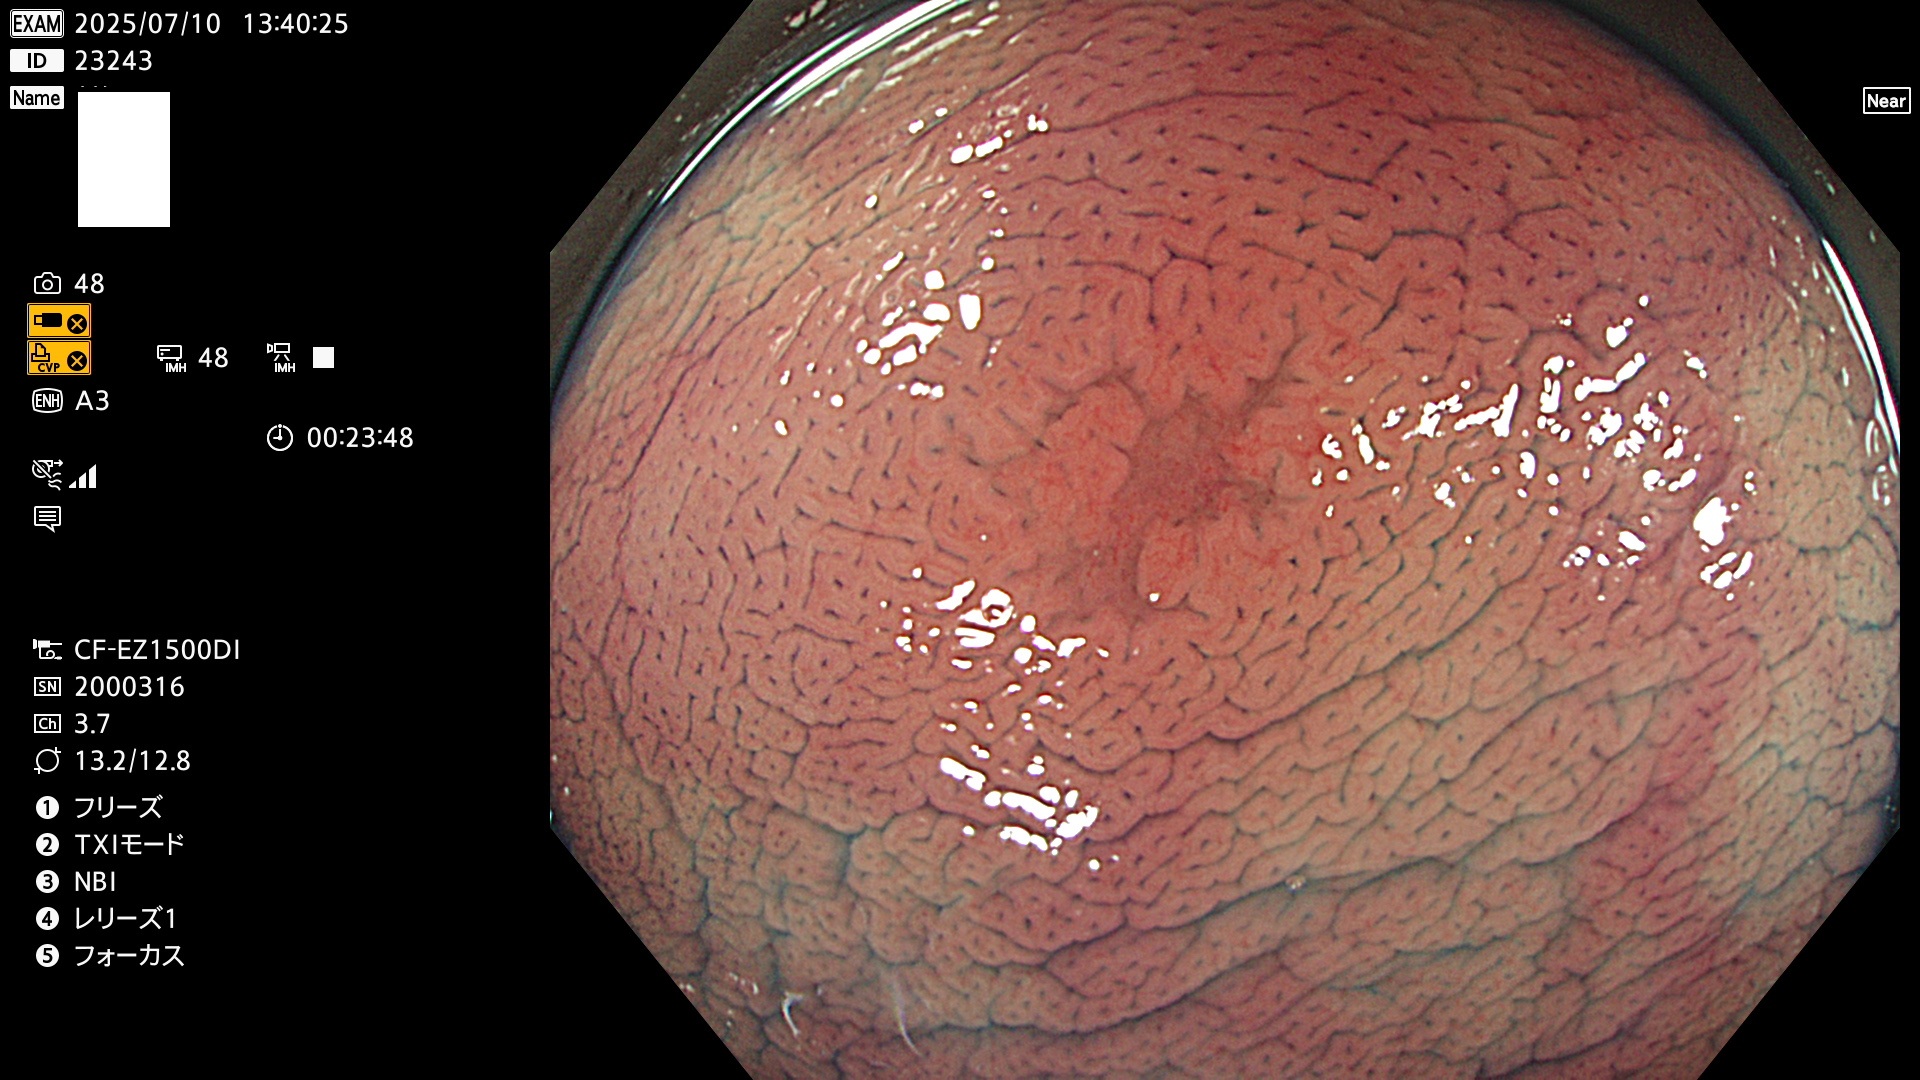

毎週の検査(木・金・土・日)に発見されたUbとUc型・腺腫を、その週の日曜の夜にUPし1週間、提示します。

2025年7月10日〜7月13日の4日間(40件)15個 (Uc_ADR=15/40=38%)